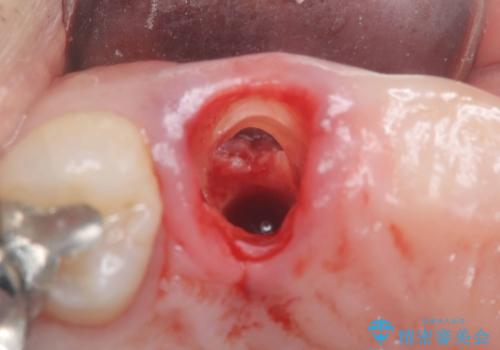

術前のCT画像より、抜歯即時インプラントが可能と判断したため、抜歯と同時にインプラント埋入を行いました。術式にはセミルーナーフラップを用い、唇側の骨吸収を抑える目的でルートメンブレンテクニックを併用しました。

抜歯即時インプラントには、切開量が少なく痛みが出にくいこと、一度の手術で治療が完了するため治療期間を短くでき、患者様の身体的負担も軽減できるという大きなメリットがあります。

今回のケースでも、しっかりと固定が得られたため、手術は1回で終了し、短期間でオールセラミッククラウンまで装着することができました。患者様も術後の痛みはなく、処方した痛み止めも服用されなかったとのことです。